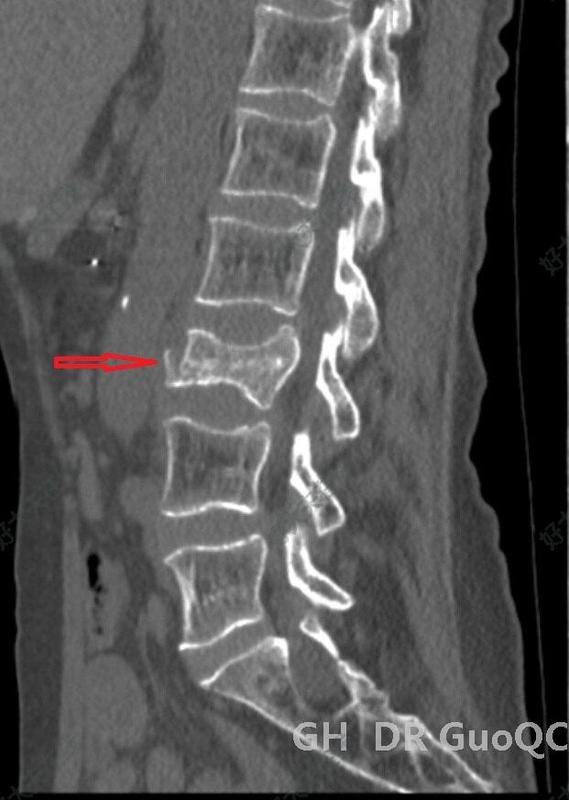

透視定位穿刺位置的好壞,是決定手術(shù)質(zhì)量的關(guān)鍵點(diǎn)。術(shù)前透視定位傷椎正位:從頭往尾,最后一節(jié)有肋骨的為T12,從尾往頭,兩髂嵴聯(lián)線齊第四腰椎棘突?!叭L(zhǎng)四翹五肥大”:一般L3橫突較長(zhǎng),L4橫突短而上翹,L5橫突較肥大。側(cè)位:楔形變,雙凹形變椎體為傷椎。例:T12上肋骨沒發(fā)育。注意:L5骶化,S1腰化,T12無肋骨的特例。以椎弓根途徑為例,皮膚進(jìn)針點(diǎn),為穿刺針針尖離椎弓根眼外緣1.5cm左右。經(jīng)椎弓根穿刺??注意穿刺針多種不同型號(hào)??引導(dǎo)絲指引??取出針芯置入引導(dǎo)絲。取出穿刺針外管沿引導(dǎo)絲放置工作通道:外鞘過椎體后緣3-5mm。建立球囊通道?使用鉆子開通道。側(cè)位相鉆子直至椎體前中1/2交界處,正位鉆頭尖位于椎弓根影與棘突連線中點(diǎn)。鉆子必須出外鞘前端2cm,保證球囊完全進(jìn)入椎體。側(cè)位像鉆頭尖在距椎體前緣2mm處停止正位顯示鉆頭尖位于棘突邊緣。去骨刺整支骨導(dǎo)向器(平口)去除通道中骨刺。骨導(dǎo)向器進(jìn)入外鞘的深度必須和鉆子的深度一致。常規(guī)消毒、鋪無菌巾,在C形臂機(jī)透視監(jiān)測(cè)下,經(jīng)雙側(cè)椎弓根穿刺,采用“步步進(jìn)針”法穿刺,即將穿刺針針尖置于椎弓根影的外上緣,一般采用左側(cè)10點(diǎn)鐘,右側(cè)2點(diǎn)鐘位置,此時(shí)側(cè)位透視針尖位于椎弓根根部。當(dāng)側(cè)位穿刺針針尖到達(dá)椎弓根的1/2時(shí),正位顯示針尖位于椎弓根影的中線處時(shí),可在側(cè)位透視下繼續(xù)鉆入。當(dāng)側(cè)位顯示針尖達(dá)到椎體后壁時(shí),正位應(yīng)顯示針尖位于椎弓根影的內(nèi)側(cè)緣,說明進(jìn)針方向正確,可繼續(xù)進(jìn)針2—3㎜后停止。退出穿刺針,依次放入擴(kuò)張?zhí)坠?,工作套管建立工作通道,?dāng)側(cè)位顯示鉆頭尖到達(dá)椎體1/2處時(shí),正位應(yīng)顯示鉆頭尖不超過椎弓根與棘突連線的1/2,當(dāng)側(cè)位顯示鉆頭尖到達(dá)椎體前緣時(shí),正位應(yīng)顯示鉆頭尖靠近棘突邊緣

胸腰筋膜(thoracolumbarfascia)是一個(gè)環(huán)帶結(jié)構(gòu),由幾個(gè)腱膜層和多個(gè)筋膜層組成,將椎旁肌與后腹壁肌肉分開。在腰椎區(qū)域,胸腰筋膜增厚,分為三層:后層、中層和前層,也有學(xué)者稱之為深層、中層和淺層,形成豎脊肌鞘和腰方肌鞘。胸腰筋膜的后層起源于腰椎棘突和棘上韌帶的尖端,分淺層和深層。其中,淺層是背闊肌的腱膜,深層覆蓋椎旁肌的后表面。中層附著在腰椎橫突的尖端,并在腰方肌后面橫向延伸。前層覆蓋腰方肌的前表面,并在腰大肌后的腰椎橫突內(nèi)側(cè)附著。在上部,胸腰筋膜附著在第十二肋骨的下緣,并延伸至腰1的橫突,形成橫膈膜的外側(cè)弓形韌帶。這三層在橫向移動(dòng)時(shí)合并為一層。腹膜后的一個(gè)常見止點(diǎn)是在第12肋骨的尖端附近,在那里胸腰筋膜各層合并為一層。這個(gè)單一的胸腰筋膜層在腹橫肌前外側(cè)與其腱膜合并。腹膜后入路可從此點(diǎn)進(jìn)入而無需切開肌肉,這是傳統(tǒng)的開放前入路的切入點(diǎn)。胸腰筋膜產(chǎn)生的“液壓放大”效應(yīng)是椎旁肌力量形成的關(guān)鍵機(jī)制。隨著背闊肌和腹橫肌的延續(xù),胸腰筋膜可以整合四肢、腹部和脊柱的機(jī)械動(dòng)作,這也是脊柱椎旁穩(wěn)定結(jié)構(gòu)的重要組成部分。胸腰筋膜可保護(hù)和維持脊柱,也參與體位變化、負(fù)荷轉(zhuǎn)移和呼吸運(yùn)動(dòng)。組織學(xué)研究表明,胸腰筋膜內(nèi)存在傷害性神經(jīng)末梢。對(duì)人類志愿者的實(shí)驗(yàn)表明,對(duì)胸腰筋膜的有害刺激可引起疼痛。人的胸腰筋膜對(duì)高滲生理鹽水的化學(xué)刺激比豎脊肌和皮下組織更敏感。一項(xiàng)研究調(diào)查了不同組織中CGRP陽性纖維的分布和密度,結(jié)果顯示胸腰筋膜中的CGRP陽性纖維密度是椎旁肌肉的三倍。大多數(shù)CGRP-和SP-ir(感覺)纖維位于筋膜外層和皮下組織。因此,胸腰筋膜可能是腰痛的重要來源。此外,炎性胸腰筋膜與完整胸腰筋膜的比較顯示,炎性胸腰筋膜中CGRP和SP陽性纖維增加,這可能解釋了病理改變的胸腰筋膜可引起疼痛。急性骨質(zhì)疏松性椎體壓縮性骨折(OVCF)患者磁共振上可見椎體骨髓水腫,T1WI低信號(hào),T2WI高信號(hào),T2加權(quán)脂肪抑制高信號(hào)。類似的水腫信號(hào)可能同時(shí)存在于胸腰筋膜及其背側(cè)皮下組織,提示OVCF合并胸腰筋膜損傷。據(jù)報(bào)道,急性O(shè)VCF患者胸腰筋膜損傷的發(fā)生率為7.4%-45%。L1骨折伴胸腰筋膜損傷由于納入標(biāo)準(zhǔn)和評(píng)估時(shí)間點(diǎn)不同,文獻(xiàn)報(bào)道的椎體增強(qiáng)術(shù)后早期殘余痛的發(fā)生率為4.6-27.9%。其中,Yang等開展的研究是文獻(xiàn)中報(bào)道的最大樣本量,其對(duì)1316例接受PVP治療的OVCF患者進(jìn)行了回顧性分析。他們將PVP后的殘余痛定義為術(shù)后立即和術(shù)后1個(gè)月VAS評(píng)分大于4分。結(jié)果發(fā)現(xiàn)術(shù)后60例(4.6%)患者出現(xiàn)殘余痛。同時(shí),單因素和多因素分析顯示,胸腰筋膜損傷是PVP術(shù)后殘余痛的一個(gè)重要危險(xiǎn)因素,OR值為3.805(p=0.002)。其他研究也發(fā)現(xiàn),胸腰筋膜損傷是椎體增強(qiáng)術(shù)(包括PVP和PKP)術(shù)后殘余痛的一個(gè)危險(xiǎn)因素,OR值分別為4.083(P=0.032)、4.11(P=0.014)和11.377(P<0.001)。然而,Yu等的研究發(fā)現(xiàn),胸腰筋膜損傷與術(shù)后殘余痛無關(guān)(P=0.31)。OVCF患者伴隨的胸腰筋膜損傷主要發(fā)生在后層,抗扭和負(fù)荷轉(zhuǎn)移過程中筋膜復(fù)合體的損傷可引起疼痛。胸腰筋膜損傷引起的疼痛通常被OVCF引起的急性和重度疼痛所掩蓋。盡管椎體增強(qiáng)術(shù)可以恢復(fù)椎體強(qiáng)度,有效改善椎體骨折引起的劇烈疼痛,但它不能減壓胸腰筋膜或改善胸腰筋膜的嚴(yán)重炎癥反應(yīng)。同時(shí),它不能穩(wěn)定胸腰筋膜,也不能恢復(fù)胸腰筋膜傳導(dǎo)負(fù)荷功能。因此,椎體增強(qiáng)術(shù)不能從根本上緩解胸腰筋膜損傷引起的疼痛,導(dǎo)致殘余痛。由于胸腰筋膜像韌帶一樣,其血液供應(yīng)遠(yuǎn)不如肌肉豐富。因此,它的愈合速度與韌帶一樣慢,可能比受傷的肌肉更容易引發(fā)慢性腰痛。一些研究發(fā)現(xiàn),恢復(fù)胸腰筋膜異??赡苄枰辽?個(gè)月的時(shí)間。此外,在一些隨訪中,有研究發(fā)現(xiàn)一些胸腰筋膜損傷患者的殘余痛持續(xù)存在,通常持續(xù)3個(gè)月以上。MRI檢查顯示胸腰筋膜損傷較術(shù)前反而明顯加重。可見,一些胸腰筋膜損傷患者不能自行愈合,甚至加重,這可能是導(dǎo)致術(shù)后持續(xù)殘余痛的重要原因。因此,骨質(zhì)疏松性椎體壓縮性骨折患者不僅要注意骨折椎體的治療,還要關(guān)注背部胸腰筋膜損傷情況。良好的胸腰筋膜功能可減少椎體增強(qiáng)術(shù)后臥床時(shí)間,對(duì)提高手術(shù)早期療效具有重要意義。Si等認(rèn)為術(shù)前MRI顯示胸腰筋膜損傷,需延遲下床。同時(shí)圍手術(shù)期對(duì)胸腰筋膜損傷應(yīng)進(jìn)行物理治療、功能鍛煉、藥物鎮(zhèn)痛等治療,促進(jìn)胸腰筋膜功能恢復(fù),縮短臥床時(shí)間,盡早下床,減少各種并發(fā)癥的發(fā)生風(fēng)險(xiǎn)。